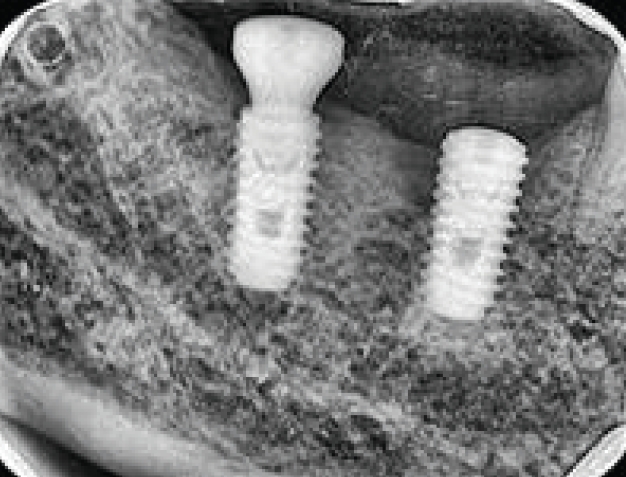

Fig. 1.

임플란트 파절

2005년까지는 국민건강보험요양급여의기준에 관한 규칙에서 치아의 보철치료(보철재료 및 기공료등 포함)는 비급여대상으로하고 있으며 보철의 범주에 속하는 임프란트 또한 비급여 대상으로, 임프란트시술 후 이와 직접 연관된 합병증 및 후유증 치료는 비급여토록 하였다. 2005년 5월 11일 진료평가심의위원회는 임프란트 치료시 최종철물을 장착하고 6개월이 경과한 후 발생한 임프란트 주위염, 임프란트 동요 및 파절 등은 이와 직접적인 진료로 보기 곤란하므로 요양급여로 인정키로 함으로서 한동안은 임프란트 주위염, 임프란트 동요 및 파절(Fig. 1) 등 3가지 경우에 한하여 기존의 건강보함항목을 적용받을 수 있는 근거가 마련되었다.